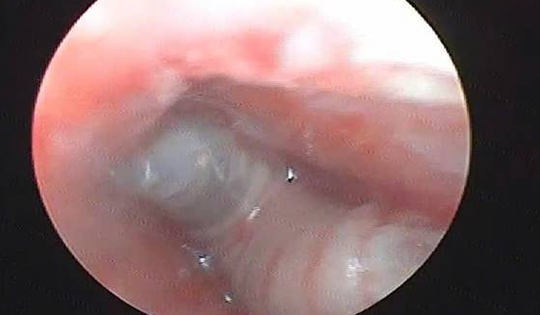

Cháu bé đau tai dữ dội, bác sĩ sốc ngang phát hiện bí mật "đáng sợ" bên trong

Cảm thấy ngứa tai rồi đau tai dữ dội, cháu bé đã đến tiệm cắt tóc để lấy dị vật nhưng không được, sau đó được người nhà đưa đến bệnh viện thăm khám. Bác sĩ bất ngờ gắp ra thứ "đáng sợ" bên trong.

Khi đang ngủ, người đàn ông 33 tuổi bị một con vật quen thuộc chui vào tai gây tổn thương niêm mạc, đau đớn dữ dội.